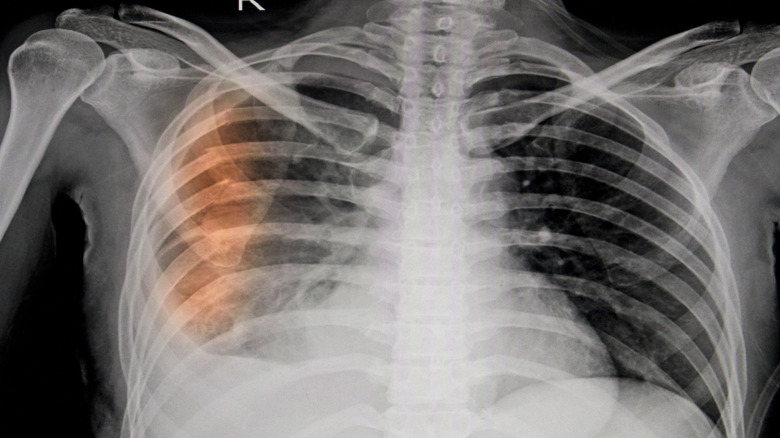

A similar problem is the damage your broken bone could do to surrounding organs. If a sharp piece of bone comes into contact with an organ, that could be a medical emergency. As examples, Better Health Channel notes that a fractured skull could send bone fragments into contact with the brain, or a fractured rib could come into contact with your heart or lungs.

There could be an embolism

Another immediate risk of a broken bone is an embolism, either a pulmonary embolism (more common) or a fat embolism (less common), according to the Merck Manual. A pulmonary embolism is what will happen when you break your hip or pelvis. This will form a blood clot, which can then break off from where it has formed within a vein. Now broken off, this clot of blood is what's known as an embolus. It moves through your circulatory system toward the lungs, where it can get stuck in an artery and stop up your blood flow. Without blood flowing freely to or from your lungs, your body is quickly deprived of oxygen, which can result in death.

Slightly less common, though still possible, is a fat embolism. This happens when a type of fat inside your bones known as marrow leaks out from the fractured bone. This fat can then go through your circulatory system to your lungs, where it forms a pulmonary embolism that stops blood from flowing through your vessels and transporting oxygen.

If you are experiencing shortness of breath or any kind of chest pain, or if your skin has turned blue, this could be a sign that you are experiencing an embolism related to your fractured bone.